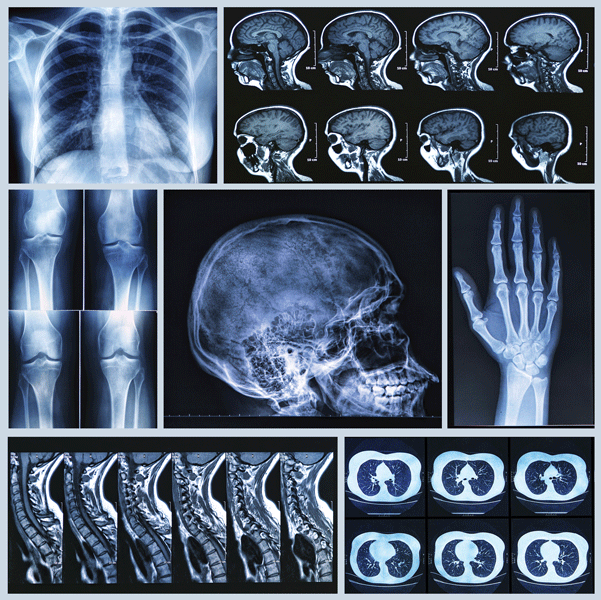

Browsing: Radiology